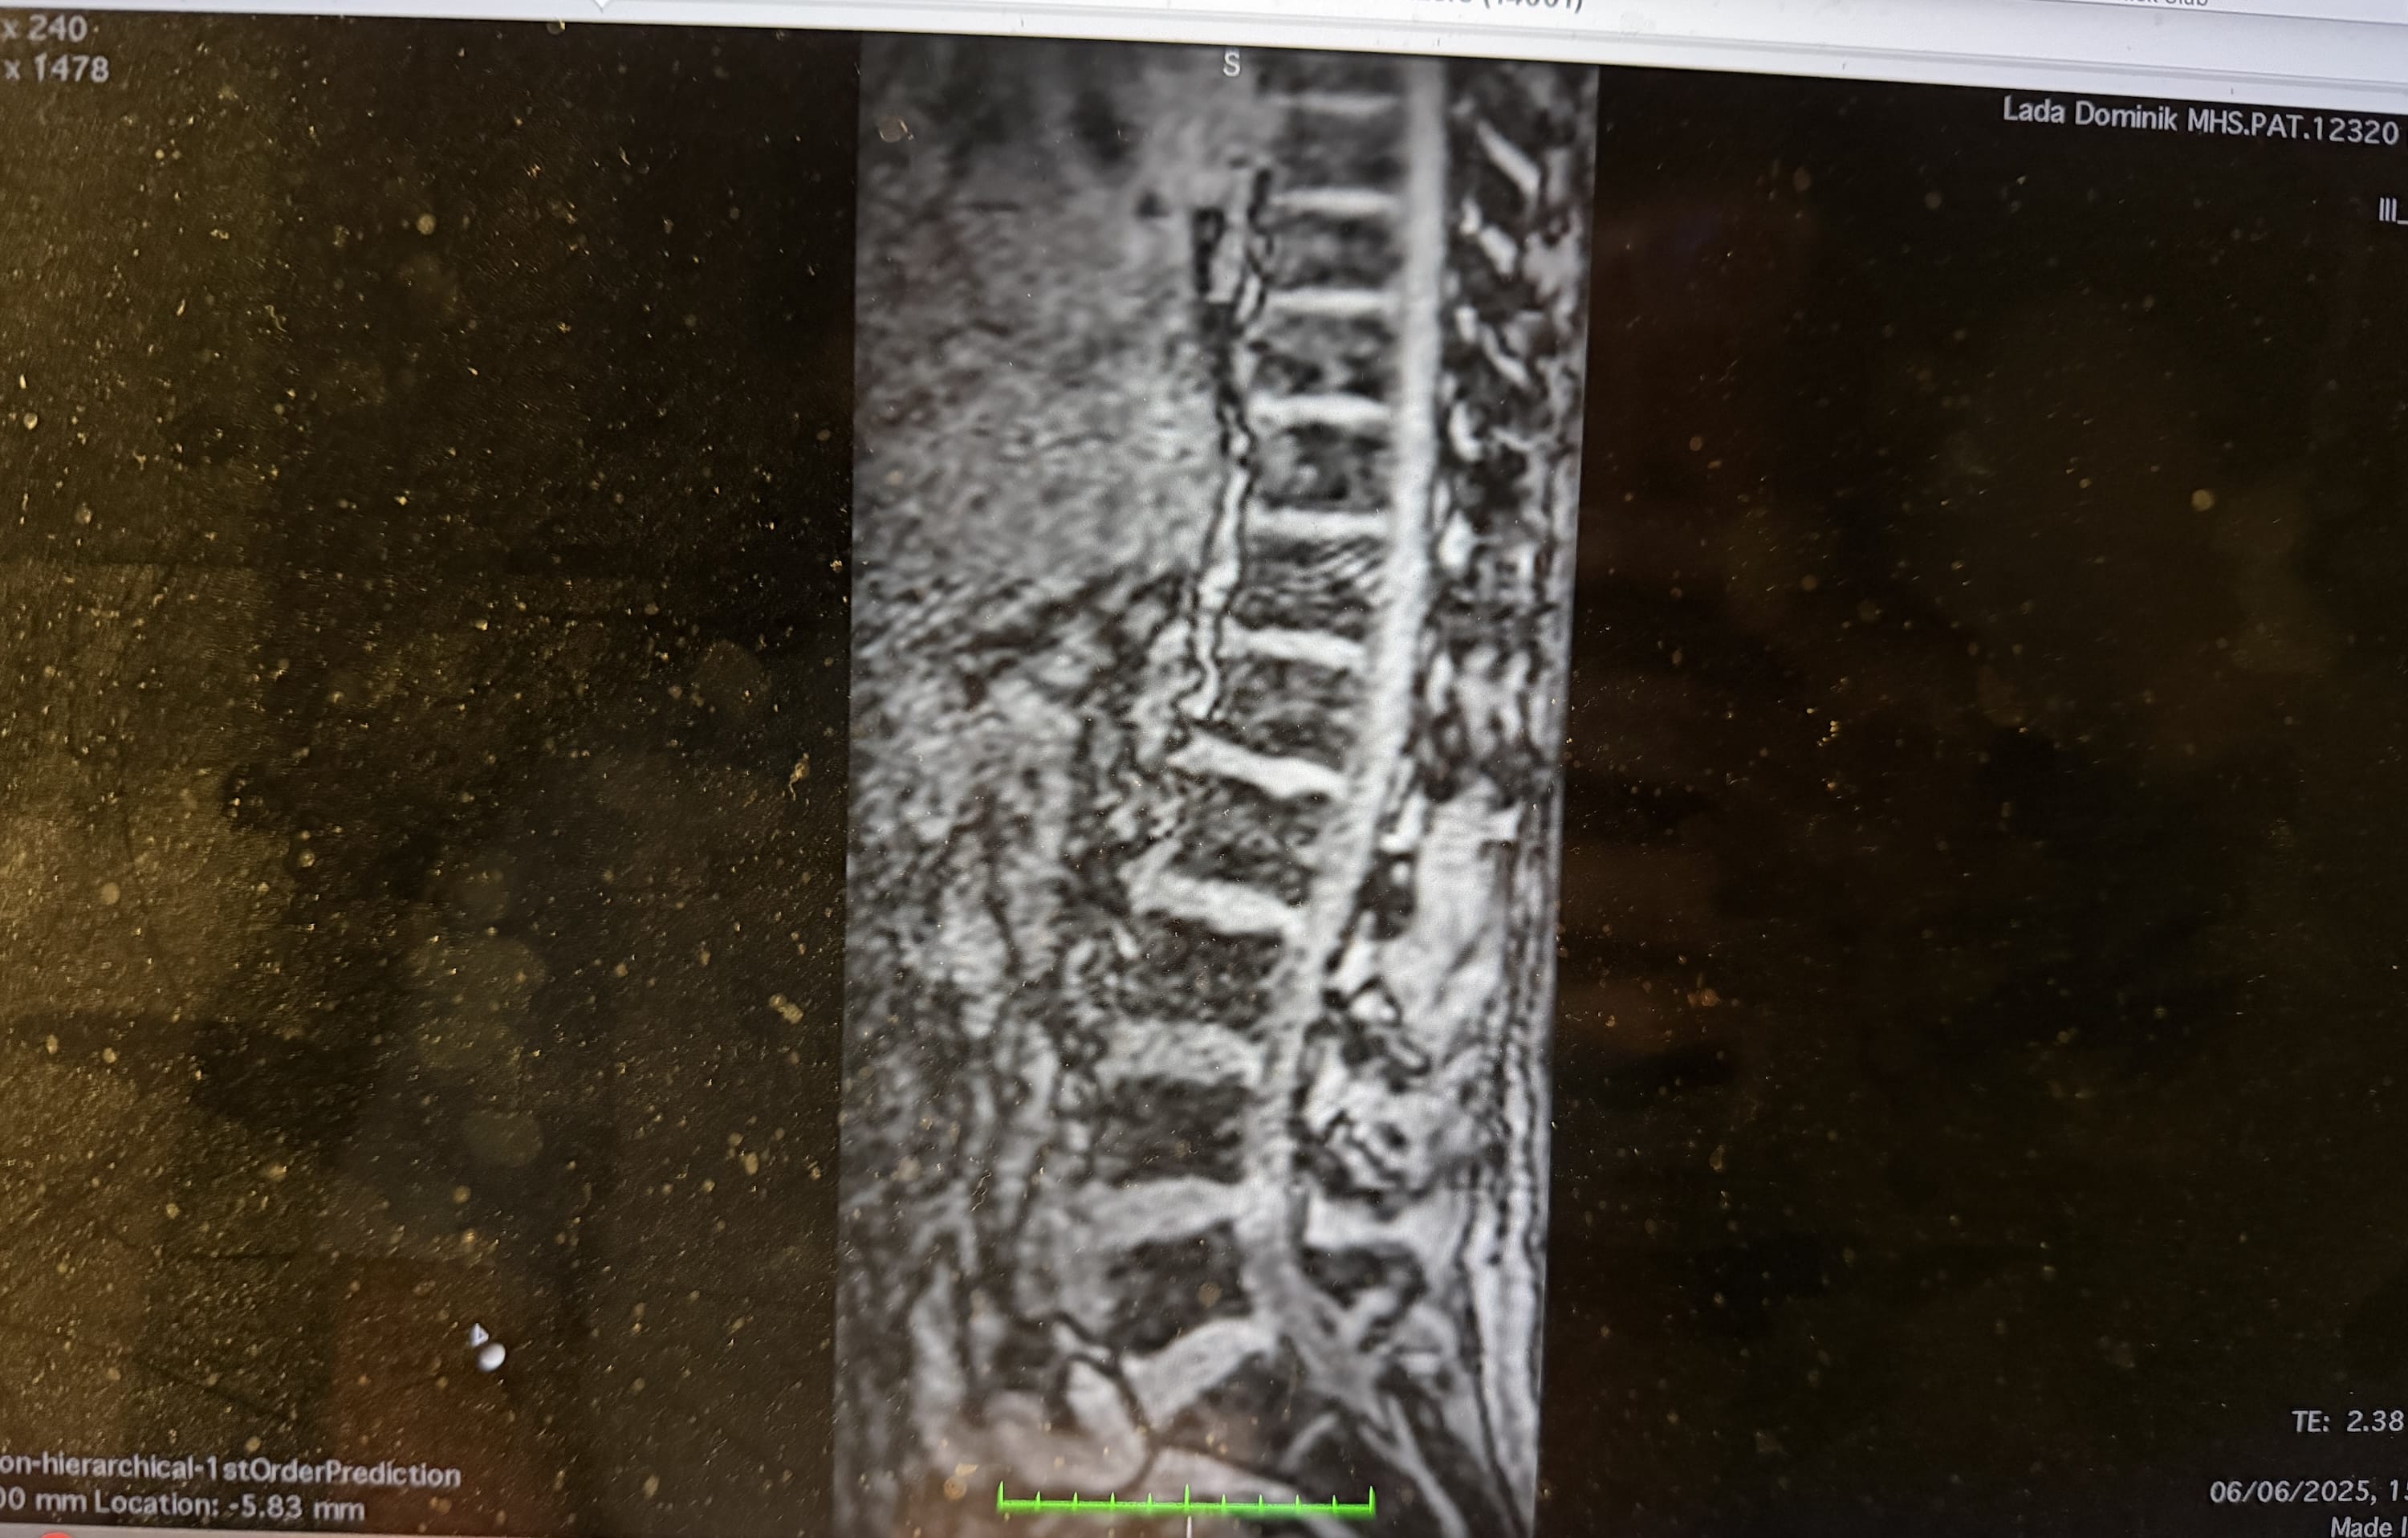

Najgorsze wydarzyło się w lutym. Po nartach – bez żadnego upadku, bez wypadku, bez jednego „konkretnego” momentu – zaczęły boleć mnie plecy. Najpierw delikatnie. Potem coraz bardziej. Aż w końcu diagnoza uderzyła jak młot:

Poważna przepuklina na odcinku lędźwiowym, z dehydratacją i krytyczną dekompresją między kręgami L4 i L5.

Brzmi źle? Bo było źle.

Od lutego bywały momenty, w których nie mogłem się ruszać. Bieganie – które uwielbiam – musiało zniknąć. Pozostałe aktywności zostały mocno ograniczone. Jedynym sportem, w którym czułem się względnie bezpiecznie, był rower.

Bilans? 1 na 3 lekarzy sugerował operację. Pozostali postawili na rehabilitację. Na szczęście – na razie – udało się operacji uniknąć.